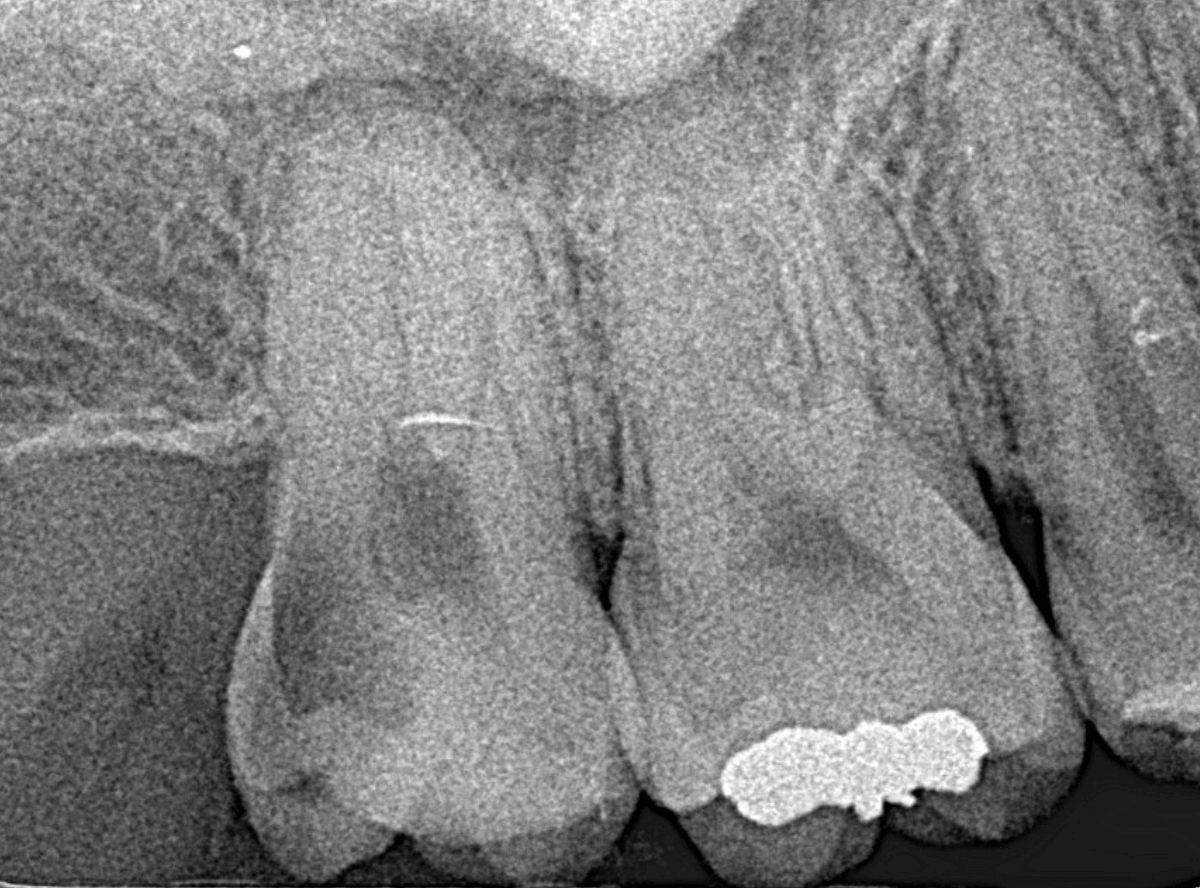

レントゲン写真です。

レジンの下が虫歯になっているのがわかります。

レントゲン写真で確認します。

青い線が歯の神経、赤い線が虫歯です。

おやしらずがあった際にはわかりづらかったですが、歯の後ろ側のおやしらずが重なっていたところが虫歯になっているのがわかります。

おやしらずが原因で、このように手前の歯が虫歯になってしまう事が多いために、抜歯を勧められる事が多いのです。

そして、虫歯の部分におやしらずが被さっていたために、しみる症状などを感じなかったのです。